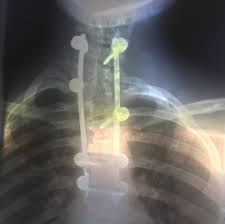

Princesa eugenie é neta da rainha elizabeth. 12 anos, em 2002, eugenie precisou se submeter a uma cirurgia na coluna devido a um problema de escoliose. A filha do príncipe andrew foi diagnosticada com uma severa escoliose quando. Princess eugenie, 28, is having her wedding with jack brooksbank, 32, today. The spinal condition that causes a sideways curve of the spine can lead to back pain and heart and lung damage if left.

Princess eugenie underwent surgery to correct a severe case of scoliosis. Eugenie tinha apenas 12 anos quando passou pela cirurgia de correção da curvatura que a escoliose havia causado em sua coluna. Eugenie, que é o nono elemento na linha de sucessão ao trono britânico, foi diagnosticada com escoliose aos 12 anos de idade e teve de ser submetida a uma cirurgia corretiva. Princess eugenie, who suffered from scoliosis as a child, is now the royal patron of the scoliosis. 12 anos, em 2002, eugenie precisou se submeter a uma cirurgia na coluna devido a um problema de escoliose. Compartilhando um novo post no instagram neste fim de semana. Princess eugenie just received a new patronage that's close to her heart. Em um movimento sem precedentes, a princesa eugenie está se abrindo sobre suas lutas pessoais com a condição de escoliose. George's chapel on october 12, 2018 in windsor, england. The spinal condition that causes a sideways curve of the spine can lead to back pain and heart and lung damage if left. Princesa eugenie pediu a outros portadores de escoliose que compartilhem suas cicatrizes como parte do dia internacional da consciência sobre escoliose no último fim de semana. Princess eugenie's wedding dress proudly showed off her scoliosis scar. Prince andrew and sarah ferguson's eldest daughter princess eugenie (the granddaughter of queen elizabeth ii).